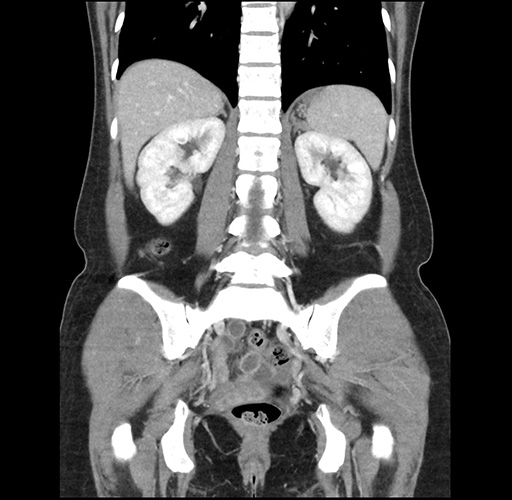

Imaging Analysis

Look through the patient's CT scan to identify any areas of concern for the necessary procedure.

Based on your CT findings, which issue(s) would give reason for "planned slowing down moment(s)" in this case?

Considering a standard left lateral sectionectomy procedure, what step(s) of the operation would you do differently in this case ?